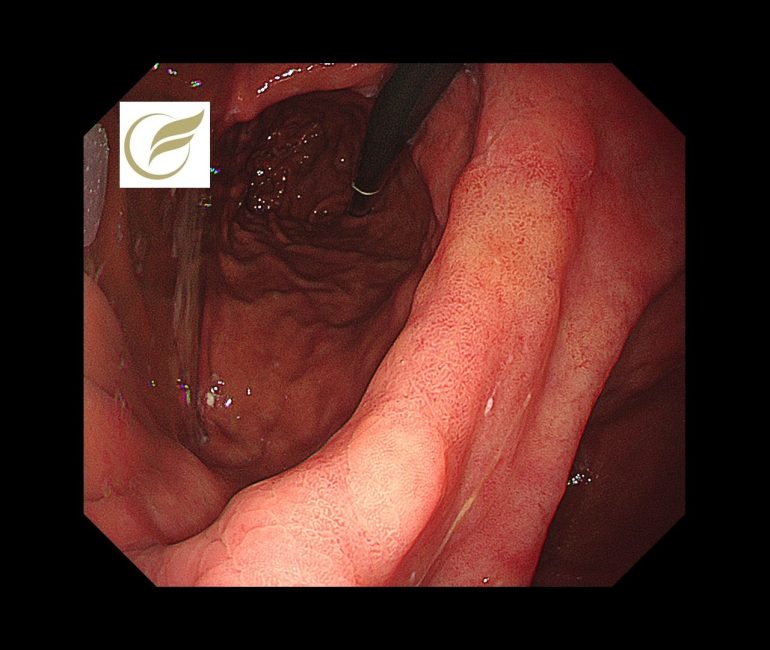

その理由のひとつに、除菌後においては背景胃粘膜の炎症が改善することで、病変と周囲粘膜との色調の差が乏しくなり発見が難しくなることがあるため(1)(4)、ときに病変が周囲粘膜に自然に溶け込むように存在し、病変と正常粘膜の境界が不明瞭となってしまうことがあげられます(4)(5)。さらに肉眼的な形態について、平坦型やごく浅い陥凹型が多く、明らかな隆起を示しにくくなる傾向があり(3)(5)、病変径が小さい上にはっきりとした陥凹を呈することがないため、典型的な悪性所見に乏しい症例も多く経験されます(1)(3)(6)。背景に萎縮や腸上皮化生を伴うことで、粘膜模様が均一化し、病変の認識がさらに難しくなることも、見逃されやすくなる原因である報告されています(4)(5)(7)。最近では、除菌後の背景粘膜が炎症軽減で均質化し病変が周囲に溶け込むような色調となった結果、除菌後胃癌が黄白色〜黄調に見えるようになるという色調・可視性に関する議論もされています(9)。除菌後症例においては、より丁寧な観察が重要となります(1)(2)(10)。

以下の病変は当院で経験された除菌後の早期胃癌(高分化型腺癌)の症例です。黄(白)色調に視認され、典型的な除菌後胃がんの特徴を示していました。